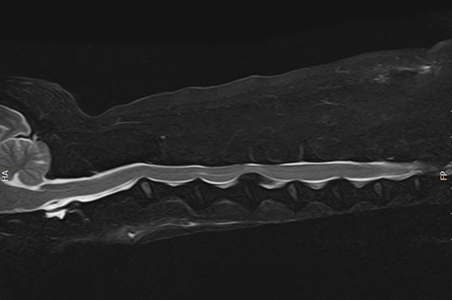

척수 및 척추 MRI

선천적인 기형, 디스크 (추간판 탈출증), 척수염, 척수연화증, 척수 출혈, 척수 및 척추 종양 등